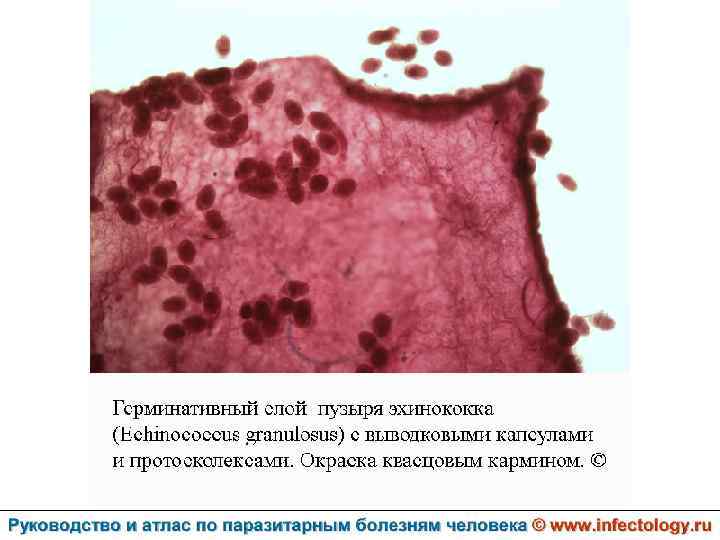

Цистный эхинококкоз (цистный гидатидоз) (шифр по МКБ 10 - B 67. 0 -4) – зоонозный биогельминтоз, характеризующийся хроническим течением, образованием кист и деструктивным поражением печени, легких и других органов.